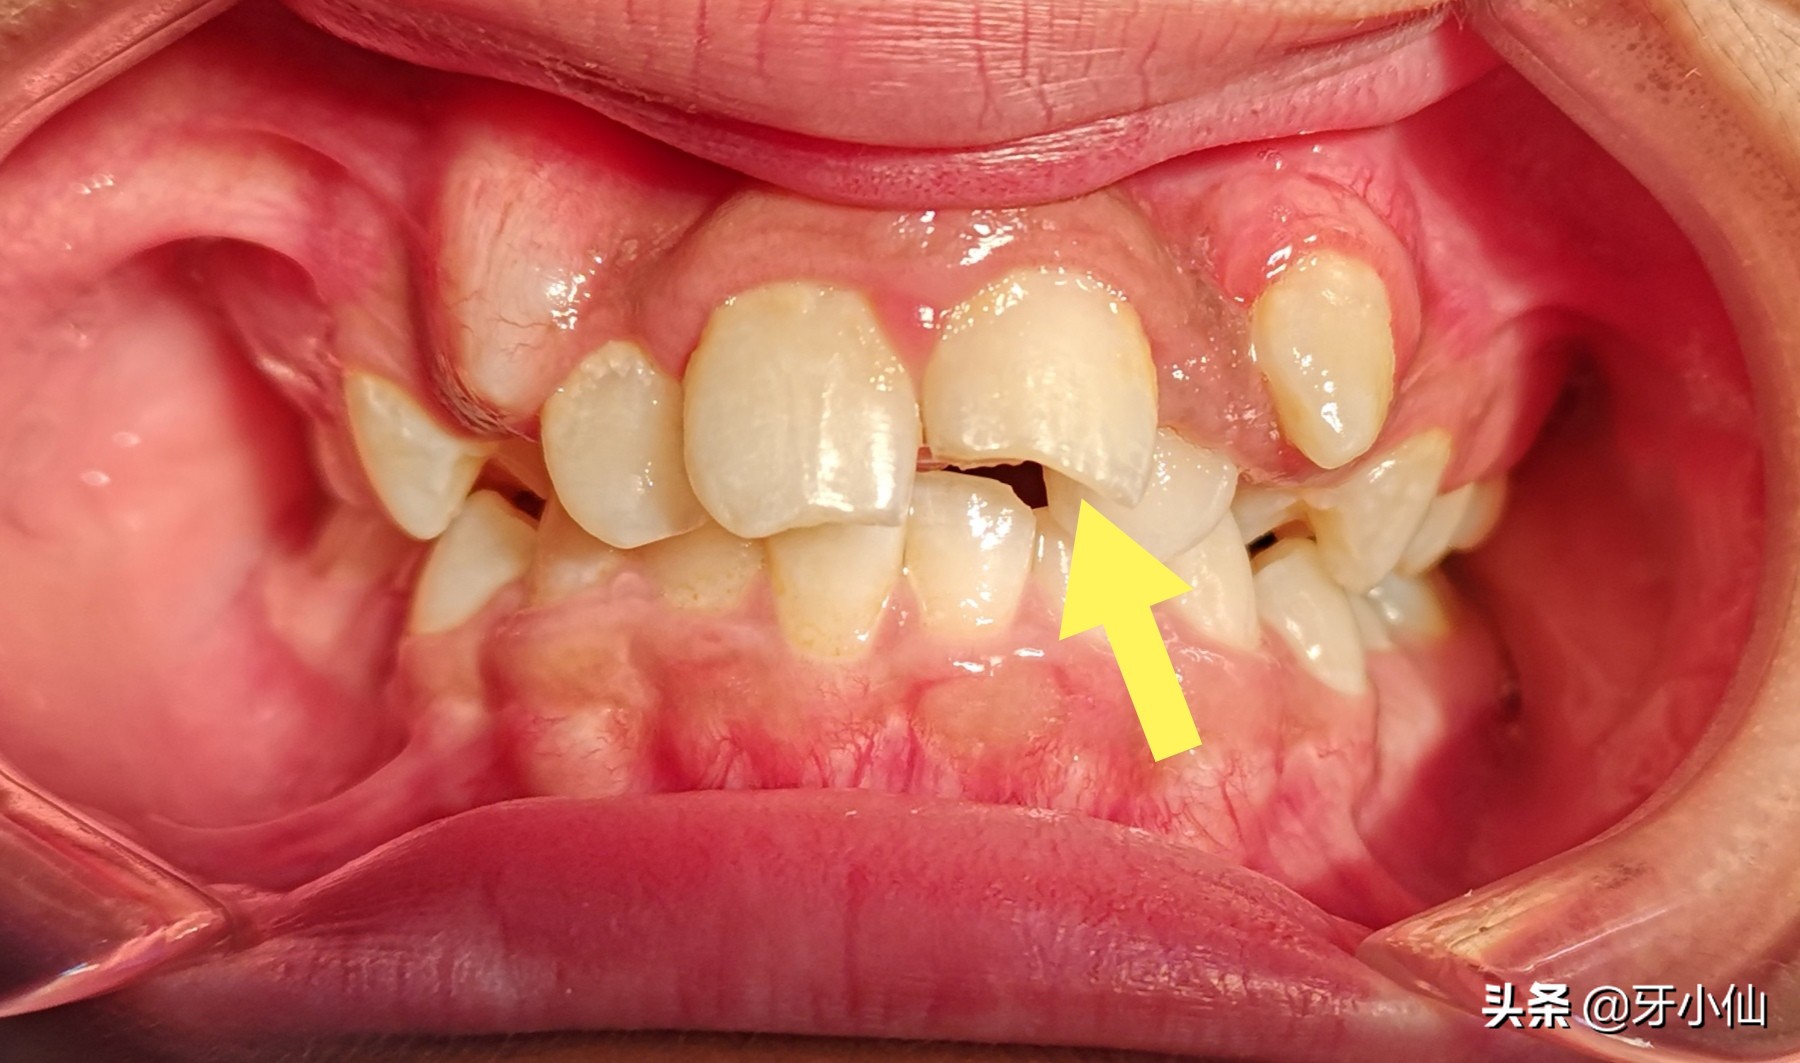

如上图所示,因为咬瓶盖、瓜子、铁丝等坚硬锋利的东西,牙齿劈开了、开叉了,牙本质和牙髓神经被暴露出来,牙髓神经直接暴露在空气中,失去了牙釉质和牙本质的保护,受到刺激,非常疼痛。

诊断为:牙裂(牙齿劈开、开叉、有缝隙)。

治疗:根据牙裂的具体情况,必要时根管治疗、冠修复(抽神经,然后包牙套),或者因为牙裂得比较严重,只能拔除了。